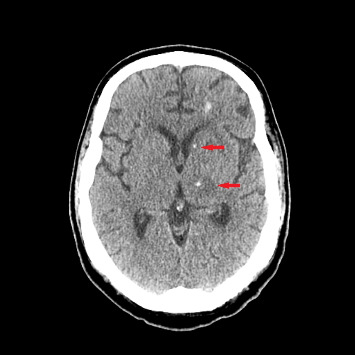

Background: Co-infection with disseminated cryptococcosis and toxoplasma encephalitis is rare but presents significant diagnostic and therapeutic challenges, particularly in severely immunocompromised patients. This case study highlights the complexities involved in managing such dual infections. Case Presentation: We describe a 43-year-old Hispanic male with Stage IV EBV-positive diffuse large B-cell lymphoma and hemophagocytic lymphohistiocytosis who presented with progressive weakness and altered mental status. Initial brain MRI revealed multiple enhancing lesions. Diagnostic tests for cryptococcosis and toxoplasma were inconclusive; however, a positive cryptococcal antigen test, new lung nodules, and potential central nervous system involvement suggested possible disseminated cryptococcosis. Diagnosis of cryptococcal meningoencephalitis could not be confirmed due to negative CSF cultures. Management and Outcome: Despite initiating treatment with amphotericin B and flucytosine for suspected cryptococcosis, the patient's condition did not improve. Initial Karius and CSF PCR tests for Toxoplasma were negative. A subsequent brain biopsy, however, confirmed toxoplasmic encephalitis. Treatment was adjusted to intravenous Trimethoprim/Sulfamethoxazole for toxoplasmosis, with continued fluconazole for cryptococcosis. The patient exhibited significant clinical improvement with this revised therapy. Conclusion: Diagnosing concurrent cryptococcal and toxoplasma infections is challenging due to overlapping clinical symptoms and variability in test sensitivities. This case underscores the need for a comprehensive diagnostic approach and the critical role of brain biopsy when other diagnostic methods, such as Karius testing and CSF PCR, are inconclusive. Prompt empirical treatment based on clinical suspicion, with subsequent treatment adjustments guided by clinical response and follow-up assessments, is essential for effective management.

Abstract Image